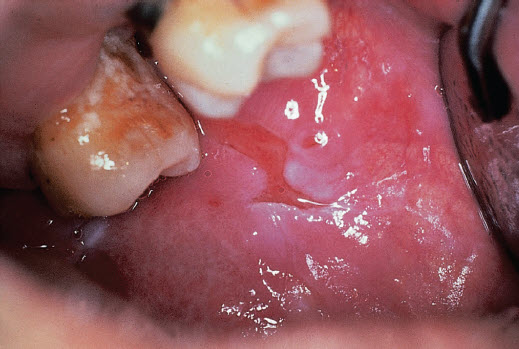

Pemphigus vulgaris: irregular persistent oral erosions.

Pemphigus vulgaris Features:

Correct Answer A: Pemphigus vulgaris is an autoimmune disease caused by antibodies directed against desmoglein, a cadherin type epithelial cell adhesion molecule. It is more common in the Ashkenazi Jewish population.